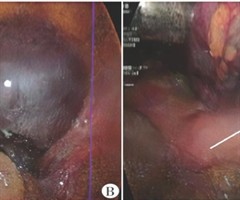

右侧卵巢性索-间质肿瘤合并蒂扭转超声表现1例

[中图法分类号]R445.1;R737.31 [文献标识码]B 患者女,39岁,孕4产1。因“右下腹疼痛,伴有恶心、呕吐等症状”入院。2年前曾发现右侧卵巢内实性肿块,未进行治疗。平素月经不规律,有痛经病史,宫内放置曼月乐环。入院前5d为末次...